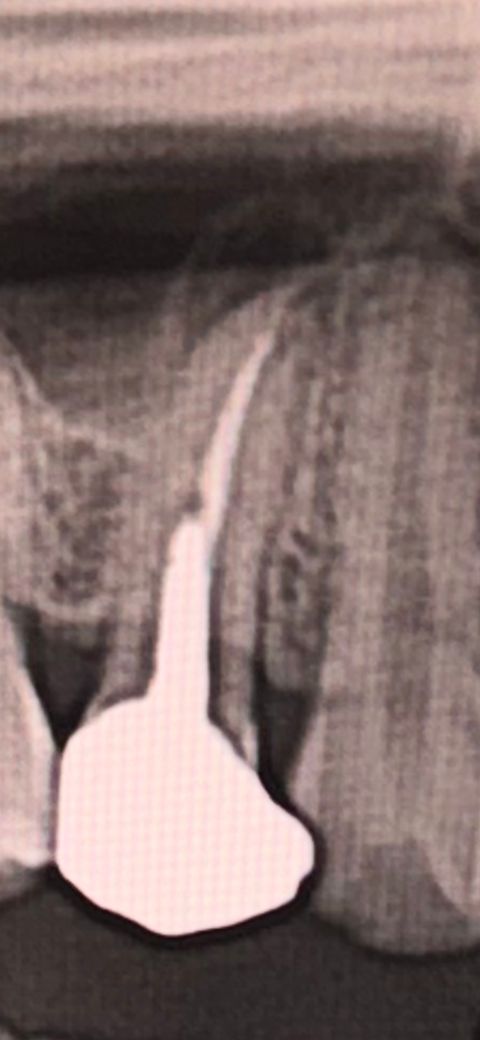

사랑니 통증 치료 하러 병원 갔다가 신경치료 했던 곳 뿌리에 염증이 있어 재신경치료나 발치가 필요하대요..

(치료할 때 기둥도 넣었던 상태)

• 1번 째 사진

사진으로 봤을 경우에는 충치가 심해서 기둥을 넣어서 치료를 한 치아로 보입니다. 기둥을 넣은 치아가 감염이 되는 원인은 여러가지가 있을 수 있지만 치암부리에 금이 갔을 가능성이 있습니다.

치아뿌리에 금이 갔을 경우 치아를 발치해야 하는 상황도 발생할 수 있기 때문에 정확한 확인을 위해서 치과에서 진료를 받아보는 것을 권해드립니다.

엑스레이상으로 염증이 있는 것으로 보이고 치아 상태도 썩 좋아보이진 않습니다. 진단을 받아보신다면 대학병원 치과보존과 한번 내원해보세요

우선 너무 걱정하고 심란해하지 마시고 신경치료한지 5년이 지났고 아무 증상이 없다면 저렇게 방사선 사진상에 뿌리끝에 염증처럼 까맣게 보이는게 무조건 문제가 있다고 보기는 어렵습니다. 보통 뿌리끝에 염증이 있는 경우에 신경치료를 하고 나면 염증이 없어지면서 뼈가 차서 사진상으로 하얗게 변하는데요. 간혹가다가 뼈가 차지 않고 다른 조직으로 대체되면서 저렇게 까맣게 보이는 경우도 있습니다. 만약 임상증상이 전혀 없고 과거 치료 후에도 저런 모습이였다면 후자의 경우처럼 다른 조직으로 대체되었을 가능성이 높고 사진으로만 봤을때에는 뿌리 끝 까만 곳 주변으로 피질골이 보여서 개인적으로는 후자일 가능성이 조금 더 높다고 보입니다.

물론 치아를 두드려 보거나 씹을때 통증이 있다면 뿌리끝에 염증이 있을 가능성이 높기 때문에 재신경치료를 하시면 되고 발치를 설명하신 이유는 아무래도 과거에 기둥(post)를 세울 정도로 치아가 얼마 남아있지 않아서 재신경치료를 위해 크라운과 post를 제거하고 재신경치료를 해야함 + 재신경 치료의 어려움 때문에 혹시 발치하게 될 가능성이 있기 때문에 고지를 해주신 것으로 보입니다.

사진상으로 보기에는 크라운과 post 주변에 충치는 없는 것으로 보아서 조심스럽게 제거하고 재신경치료를 하면 발치까지는 가지 않을 가능성이 높기 때문에 너무 걱정하지마시고 추후에 해당 치아의 재신경치료 문제로 치과에 내원하실 예정이시라면 셋 중에서는 치과보존과 전문의 원장님께 진료를 받으시는 것을 추천드립니다.